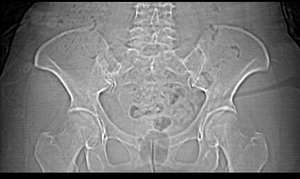

女,55岁,因下腹胀痛2月,b超发现盆腔包块7天,而入院,检查:右侧附件如女拳头大小包块,活动差,轻压痛,质中,子宫稍正常缩小,彩超示子宫4.9cmx2.6cmx2.3cm ,右侧附件包块示:8.7cmx9.1cmx6.3cm 的混合性回声,脂质分层征

囊性畸胎瘤的液-液征,增强瘤结节强化。

畸胎瘤,可见典型脂肪-液体征象。

畸胎瘤,脂-液分层